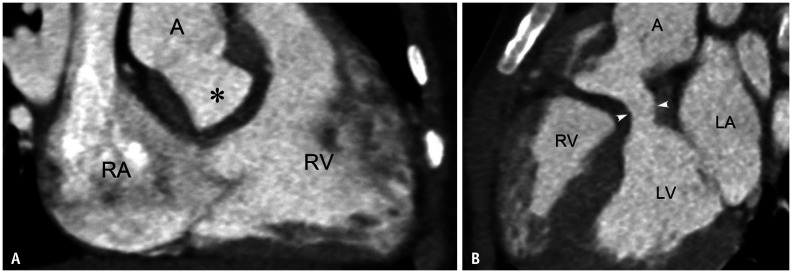

Fig. 20. Postoperative left ventricular outflow tract obstruction developed after intraventricular baffling to A in a 3-year-old boy with double outlet RV and non-committed ventricular septal defect.

A. RV long-axis CT image shows the unobstructed right ventricular outflow tract and the intraventricular baffle (asterisk). B. LV long-axis CT image demonstrates the left ventricular outflow tract obstruction (arrowheads). A = ascending aorta, LA = left atrium, LV = left ventricle, RA = right atrium, RV = right ventricle